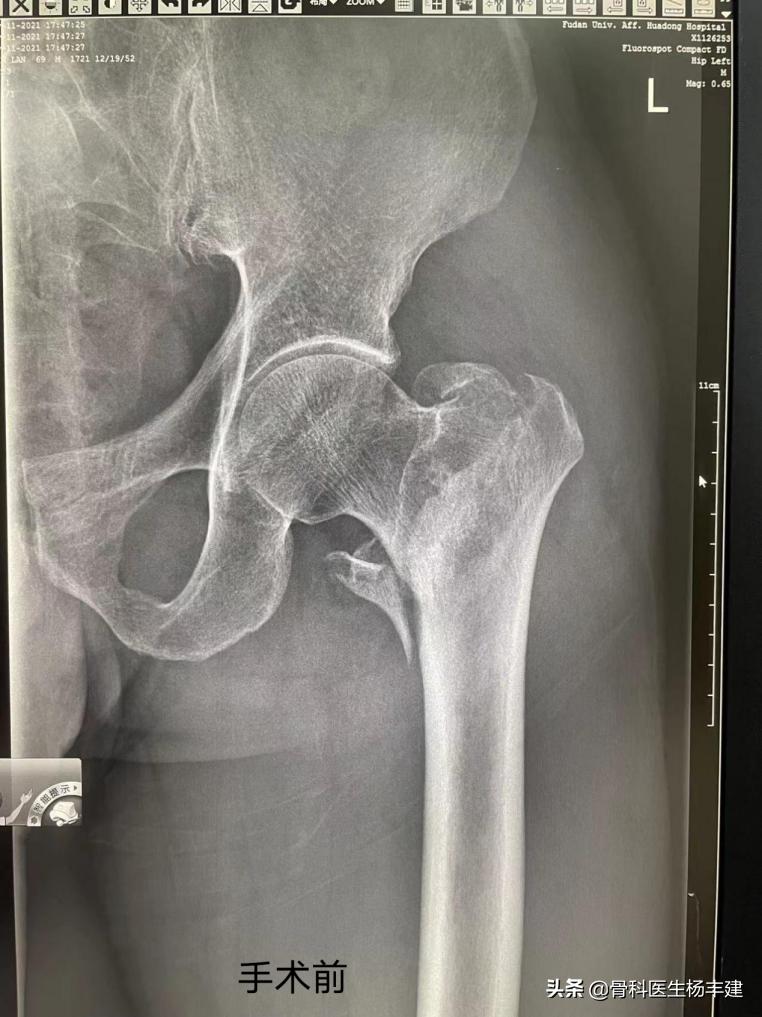

那天,老先生早起晨跑时摔了一跤,觉得左边外侧大腿根部疼痛,就来医院看急诊。通过X光检查后发现,老先生疼痛的原因是股骨粗隆间骨折(也称为股骨转子间骨折)了,这种骨折人们通常也叫它“大腿骨骨折”。

老先生住院后接受了股骨粗隆间骨折的内固定手术,手术方式是闭合复位髓内钉内固定术,就是通过螺钉,固定住断裂的骨头,让关节恢复完整的连接,恢复接近正常的功能。这是一种微创手术方法,只需要开三个1-3厘米大小的小口子就行,顺利的话半小时就能结束手术。具有创口小、损伤少、手术时间短、恢复快的优点。